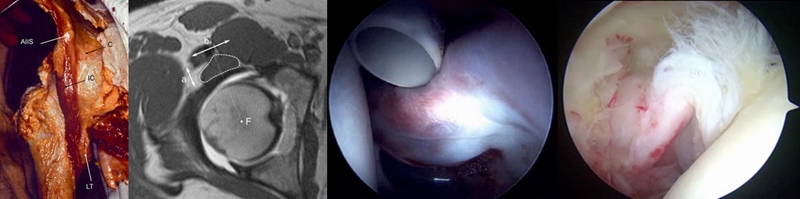

除了骨性结构的表现之外,与髋关节稳定相关的一些软组织结构,也逐渐来到大家的视线之内。包括前几年逐渐被证实的髂关节囊肌,它的增厚可能会反映髋关节发育不良的情况。另外还有关节内盂唇肥厚,以及圆韧带退变、撕裂等形态性的改变,也可能和髋关节不稳相关。

最近,对于关节囊韧带的认识逐渐加重了,尤其对于前方关节囊,它是否跟髋关节稳定性也有密切联系,这个答案应该是比较肯定的。

除厚度测量之外,也借助半月板的信号分级对前关节囊进行了内部信号分级。临床分为0~4级,正常表现是0级,出现点状信号为1级,出现线状信号为2级,出现断裂或者明显的贯通样分层为3级。